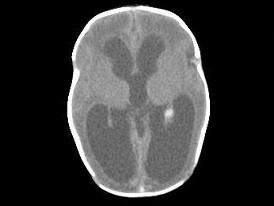

问题 1岁,女,头颅呈球状,颅骨透光试验阳性,请结合CT图像选择最可能诊断 ( )

选项 A、先天性脑积水 B、外部性脑积水 C、慢性双侧性巨大硬膜下血肿 D、水瘤 E、脑严重缺血

答案 A